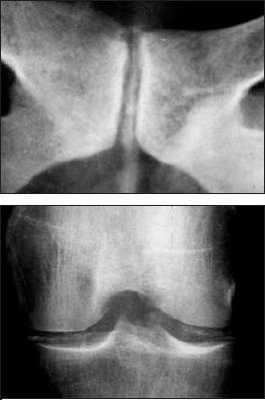

Болезнь отложения кристаллов кальция пирофосфата дигидрата (БКПД) в медицинской литературе известна под тремя названиями: «псевдоподагра», «хондрокальциноз» и «пирофосфатная артропатия». Однако приведенные определения явно не удовлетворяют современным требованиям к номенклатуре заболеваний, стремящимся к максимально полной характеристике патологического процесса. Так, термин «псевдоподагра» точно описывает клинические проявления бурного синовиального воспаления при БКПД, схожего с атакой подагрического артрита, но подобные приступы наблюдаются далеко не у всех пациентов. Термин «хондрокальциноз» описывает рентгенологическую картину отложения кристаллов пирофосфата кальция в гиалиновом хряще и других внутрисуставных структурах (менисках), наблюдаемую у пациентов с БКПД. Однако данные рентгенологические признаки (кальцификация мягких тканей) могут наблюдаться и при других состояниях. Наконец, наиболее часто встречающийся термин «пирофосфатная артропатия» свидетельствует о существующем в течение длительного времени определенном агностицизме в представлениях врачей о данном заболевании. Распространенность . БКПД - это болезнь пожилых людей, со средним возрастом пациентов 70 лет. В этом возрасте отложения пирофосфата кальция в гиалиновом хряще являются нередкой находкой. Эпидемиологические исследования (включавшие рентгенологическое обследование коленных суставов, суставов кистей и таза) свидетельствуют о прямой связи распространенности суставного хондрокальциноза с возрастом: в 65-74 года хондрокальциноз обнаруживают у 15%, в 75-84 года - у 36%, в возрасте более 84 лет - почти у 50% обследуемых независимо от присутствия симптомов. Данные по более молодым возрастным группам отсутствуют. Причины отложения кристаллов пирофосфата кальция при старении хряща остаются неясными. Отчетливых половых различий в частоте БКПД не найдено, однако вариант «псевдоподагры» наблюдается чаще у мужчин, а «псевдоостеоартроза» - у женщин. Отложение кристаллов кальция пирофосфата дигидрата представлено на рентгенограммах. Патогенез . Основным патогенетическим механизмомБКПД является образование и накопление кристаллов пирофосфата кальция . Пирофосфат (дифосфат) кальция диг и д р а т , Са2(Р2О7)2Н2О, представляет собой естественную неорганическую соль кальция, присутствующую в тканях организма. Патогенез БКПД кардинальным образом отличается от патогенеза подагры - другого распространенного заболевания из группы микрокристаллических артритов. Если при подагре образование кристаллов уратов происходит в синовиальной жидкости или во внесуставных тканях (формирование тофусов) на фоне общего повышения уровня мочевой кислоты в тканевой жидкости, то при БКПД первичной зоной кристаллообразования является толща гиалинового или волокнистого хряща при нормальном уровне кальция в других тканях организма. В норме этот процесс наблюдается при физиологической минерализации хрящевой пластинки в период роста кости, но нормальный гиалиновый хрящ не кальцифицируется. В течение последнего времени получены определенные данные, проясняющие патогенез БКПД. Установлено, что образование кристаллов пирофосфата начинается в зоне хряща, прилегающей непосредственно к мембране хондроцитов. Образование и накопление кристаллов пирофосфата могут быть результатом как повышенного локального уровня кальция, так и изменений в перицеллюлярном матриксе (протеогликанах и коллагене), приводящих к перенасыщенности присутствующего здесь пирофосфата кальция или комбинацией этих факторов. Современные достижения в молекулярной патологии и гистохимии определили потенциальные факторы, участвующие в этом процессе. Типичными морфологическими признаками, предшествующими минерализации хряща в ростовой пластинке кости, являются гипертрофия хондроцитов и их усиленный апоптоз . Эти же признаки наблюдаются в хряще при остеоартрозе (ОА) и описаны, как самые ранние морфологические признаки БКПД. Механизм связи между интенсивной продукцией протеогликанов гипертрофированными хондроцитами и образованием кристаллов при БКПД неясен. Однако электронно-микроскопические и иммунохимические исследования показали, что в гипертрофированных хондроцитах при БКПД присутствуют измененные протеогликаны, меньшего размера в сравнении с нормой, и дегенеративно измененные короткие цепиколлагена. При гипертрофии хондроцитов имеет место избыточная продукция коллагена X типа, матриксной металлопротеиназы-13 и щелочной фосфатазы, которые также влияют на процесс кальцификации. Показано, что гипертрофия хондроцитов сопровождается изменениями в продукции трансглютаминазы, фермента - представленного двумя типами: трансглютаминазой-2 (ТГ2) и фактором XIIIА. Функция трансглютаминаз заключается в посттрансляционном образовании поперечных связей в белках, происходящем как внутриклеточно, так и во внеклеточном матриксе. Наличие поперечных связей в кальций-связывающих белках постулируется как условие стабилизации матрикса и минерализации хряща ростовой пластинки. Трансглютаминазы могут модулировать кальцификацию хряща непрямым образом посредством активации мощного кристаллообразующего фактора - ростового фактора- ? . На животных моделях показано, что хондроциты гиалинового хряща экспрессируют ТГ2 и фактор XIIIА и что их активность усиливается с возрастом. ТГ2 ответственна за увеличение концентрации неорганического пирофосфата в экстрацеллюлярном пространстве хондроцитов и является основным регулятором процесса кальцификации хряща. Эти данные были подтверждены гистохимическими исследованиями на тканях человеческого мениска и суставного хряща при ОА; нарушения регуляции ТГ2 и фактора XIIIА были обнаружены как в поверхностной и глубокой зонах хряща при ОА, так и в центральной зоне дегенеративного мениска. Определенным образом в патогенезе БКПД играют роль генетические факторы. Известна семейная форма БКПД, при которой хондрокальциноз регистрируется у членов одной семьи в более молодом возрасте, чем в среднем в популяции. Существует линия мышей ( «tiptoe-walking» mouse ), характеризующаяся точечной мутацией, приводящей к дефициту фермента фосфодиэстеразы; при этом наблюдается избыточная минерализация осевого скелета. Состояния, ассоциированные с хондрокальцинозом В отличие от истинной БКПД существуют состояния, при которых отложение кристаллов пирофосфата кальция в хряще лишь сопровождает основной патологический процесс. К ним относятся травматические поражения суставов, ряд метаболических и эндокринных заболеваний, которые необходимо исключать при постановке диагноза БКПД, особенно при начале клинических проявлений в молодом возрасте. В частности, при обнаружении хондрокальциноза в отдельных суставах у молодых людей необходим тщательный сбор анамнеза, в ряде случаев позволяющий связать этот признак с предшествующей травмой сустава или хирургическим вмешательством на нем. Патогенез посттравматического кальциноза мягкотканых структур суставов (менисков в коленных и треугольного хряща в лучезапястных) идентичен наблюдаемому при естественной инволюции гиалиного хряща. Хондрокальциноз встречается при гемохроматозе - относительно редком заболевании, спектр признаков поражения опорно-двигательного аппарата при котором близок клиническим проявлениям БКПД (псевдоподагра, хондрокальциноз, хроническая артропатия). Влияние накопления железа в тканях организма на патологическую минерализацию также подтверждается обнаружением отложений кристаллов пирофосфата в суставах при гемосидерозе и гемофилической артропатии. Другие состояния и предрасполагающие факторы . Помимо гемохроматоза, известен ряд других метаболических и эндокринных заболеваний, ассоциированных с отложением кристаллов пирофосфата кальция. Обнаружение рентгенологических и клинических признаков БКПД всегда требует исключения этих состояний, особенно у молодых пациентов (табл. 1). Описаны случаи развития острого суставного воспаления, связанного с кристаллами пирофосфата, после внутрисуставного введения гиалуроната и внутривенного введения памидроната. Возможной причиной может быть нарушение равновесия между концентрациями фосфата кальция в синовиальной жидкости и окружающих тканях, приводящее к выбросу (или образованию) кристаллов в полость сустава. Клиника БКПД представлена несколькими клиническими вариантами. Наиболее часто встречается «псевдоостеоартроз» , характеризующийся умеренными болями (преимущественно механического ритма) в пораженных суставах (наиболее часто - коленных), ограничением подвижности. Также как при ОА, дегенеративный процесс может сопровождаться формированием остеофитов (узелки Бушара и Гебердена) и варусной деформацией коленных суставов (в ряде случаев вызванной асептическим некрозом медиальных мыщелков). Рентгенологические признаки хондрокальциноза обнаруживаются во многих суставах, однако клиническая значимость определяется поражением отдельных суставов, чаще всего коленных. Симптомы воспаления присутствуют (как и при идиопатическом ОА), но носят умеренный характер и не отражаются на лабораторных показателях. Признаками, позволяющими провести дифференциальный диагноз в пользу псевдоостеоартрозного варианта БКПД, являются необычная для ОА локализация пораженных суставов (лучезапястные, локтевые, плечевые, пястно-фаланговые, голеностопные суставы) и рентгенологически выявляемый в пораженных суставах хондрокальциноз. Сложным и в ряде случаев неразрешимым вопросом является интерпретация рентгенологических признаков БКПД (хондрокальциноза), определяемых у пациентов с типичной для ОА локализацией пораженых суставов - коленных, межфаланговых суставов кистей, у которых клинические проявления ОА появились раньше, чем рентгенологически регистрируемый хондрокальциноз. Сравнение данных рентгенологического исследования пораженных суставов за несколько лет и фиксирование лишь последующего появления хондрокальциноза на каком-то этапе дегенеративного процесса позволяют сделать вывод о вторичности отложения пирофосфата кальция в пораженном хряще. «Псевдоревматоидная» форма БКПД наблюдается у 5% пациентов и характеризуется симметричным поражением пястно-фаланговых суставов, обычно II-III пальцев, протекающим с утренней скованностью, иногда с формированием сгибательных контрактур и умеренным повышением острофазовых показателей. Однако в отличие от истинного ревматоидного артрита наблюдается лишь умеренное воспаление, отсутствие эрозий суставных поверхностей и хондрокальциноз. «Псевдоподагрический» вариант представляет собой наиболее известное и яркое проявление БКПД. Бурное микрокристаллическое воспаление возникает в ответ на высвобождение значительного количества кристаллов кальция пирофосфата из толщи хряща в синовиальную полость. Выраженность воспаления и его кратковременность (несколько дней, редко более недели) определили название этого варианта БКПД. Данный вариант БКПД традиционно фигурирует в перечне причин острого моноартрита (две другие - подагра и инфекционный артрит). В отличие от истинной подагры первый приступ возникает в возрасте 50 лет и старше (исключение - семейная наследственная форма БКПД), воспаление практически всегда локализовано в коленных суставах, реже в других и крайне редко - в I плюснефаланговом суставе. Женщины страдают этой формой БКПД почти с такой же частотой, как и мужчины. Как и при истинной подагре, провоцирующими факторами могут быть травма, хирургическое вмешательство, нарушение мозгового кровообращения и инфаркт миокарда. Отмечена сезонность - приступы достоверночаще возникают весной. До и между приступами острого воспаления сустав, как правило, асимптоматичен. Однако возможно развитие приступа острого воспаления отдельных суставов и у пациентов с «псевдоостеоартрозной» формой БКПД. Наиболее редко (описаны единичные случаи) БКПД проявляется псевдонейропатической артропатией , обычно коленных суставов, при которой формируется клиническая и рентгенологическая картина артропатии Шарко. В отличие от истинного сустава Шарко (встречающегося при tabes dorsalis и сирингомиелии) эта форма БКПД не сопровождается признаками поражения центральной и периферической нервной системы. Асимптомный хондрокальциноз , как уже указывалось, нередко обнаруживается у пожилых людей. У пациентов с клиническими признаками БКПД в отдельных суставах хондрокальциноз может быть выявлен и в других, клинически интактных, суставах. Считать ли асимптомный хондрокальциноз болезнью? По-видимому, здесь справедлива та же позиция, которая в настоящее время существует в отношении рентгенологических проявлений и диагноза остеоартроза - «нет симптомов - нет болезни». Подобная аналогия представляется уместной, так как и рентгенологические проявления остеоартроза (остеофиты, сужение суставной щели) и хондрокальциноз имеют отчетливую корреляцию с возрастом и могут представлять собой варианты естественной инволюции опорно-двигательного аппарата, не сопровождающиеся клиническими симптомами. Известно, что выраженность клинических проявлений БКПД не связана с выраженностью хондрокальциноза. Лечение В связи с неясностью до настоящего времени точного механизма, приводящего к формированию и накапливанию кристаллов пирофосфата кальция в гиалиновом хряще, патогенетических методов лечения этого заболевания не существует. При псевдоостеоартрозе применяется тот же комплекс лечебных мероприятий, что и при идиопатическом ОА, включающий разгрузку пораженных суставов, укрепление мыш, стабилизирующих пораженный сустав, симптоматический прием нестероидных противовоспалительных препаратов с учетом переносимости сопутствующей патологии. Принимая во внимание, что патогенез БКПД имеет общие детали с ОА (продукция хондроцитами дефектных протеогликанов), теоретически при БКПД можно ожидать эффект от приема структурно-модифицирующих препаратов, применяемых при ОА (глюкозамин, хондроитин, гиалуроновая кислота). Однако на сегодняшний день результаты подобных исследований не публиковались. Тактика при развитии острого воспаления, определяющего клинику псевдоподагры заключается, прежде всего, в исключении инфекционного артрита . Методом, позволяющим это сделать, является исследование синовиальной жидкости, включающее бактериологическое (окраска по Граму и посев) исследование и поиск в жидкости кристаллов. Визуальная характеристика синовиальной жидкости и обычное цитологическое исследование не позволяют провести дифференциальный диагноз между этими заболеваниями - высокий цитоз (вплоть до пиоидности) и преобладание нейтрофилов характерны как для БКПД, так и для инфекционного воспаления. При определенном опыте исследователя кристаллы пирофосфата кальция могут быть идентифицированы при обычной световой микроскопии (в отличие от игловидных уратов они имеют вид параллелепипедов с «обрубленными» концами, ромбов). Более достоверным способом обнаружения и идентификации кристаллов является микроскопия в поляризованном свете с применением компенсатора , при которой определяется способность кристаллов пирофосфата к слабому двойному лучепреломлению (рис. 1). Исследование в поляризованном свете позволяет обнаружить кристаллы пирофосфата кальция в 5 раз чаще, чем при обычной микроскопии. Диагноз значительно упрощается при развитии повторных приступов. Собственно, лечение приступа псевдоподагры не отличается от такового при остром приступе подагры. Эффективны традиционные НПВП, применяемые в средних и максимальных дозах. Среди современных комбинированных противовоспалительных средств, эффективных при остром приступе псевдоподагры, хорошо себя зарекомендовал Амбене - препарат, сочетающий мощную противовоспалительную активность глюкокортикостероида (дексаметазона) и НПВП (фенилбутазона), позволяющих быстро купировать приступ. Амбене выпускается в двух лекарственных формах (готовые шприцы и двойные ампулы) и назначается однократно в сутки, коротким курсом 3 инъекции в неделю ежедневно или через день. При затяжном приступе (длящемся более 3 дней, несмотря на энергичную противовоспалительную терапию) или при противопоказаниях к использованию НПВП методом выбора является введение в сустав адекватной дозы микрокристаллического глюкокортикостероида пролонгированного действия - триамцинолона ацетонида или бетаметазона дипропионата. Как правило, данная процедура проводится однократно, крайне редко возникает необходимость в повторном введении. Применение колхицина, как противорецидивного препарата при псевдоподагре, не получило распространения в связи с плохой переносимостью и отсутствием данных о его эффективности. Не подтвердилась эффективность солей магния, попытки введения которых в сустав при приступе псевдоподагры предпринимались с целью перевода кристаллов пирофосфата кальция в растворимое состояние. Таким образом, БКПД представляет собой известную, но до настоящего времени во многом загадочную нозологическую форму. Встреча с пациентом с предположительным диагнозом БКПД требует от врача как умения взвешенно подходить к интерпретации выявляемых инструментально признаков патологии (хондрокальциноза, обнаружения кристаллов пирофосфата кальция в синовиальной жидкости), так и (при подтверждении диагноза) определять тактику лечения для каждого пациента исходя из принципов достаточности и безопасности.